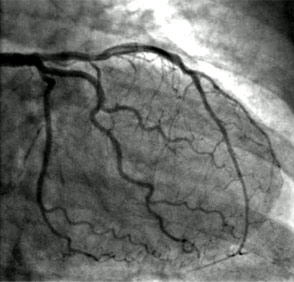

Angiogram(also known as coronary angiogram or cardiac catheterisation)

Coronary angiogram is a procedure to look at the arteries in the heart (called coronary arteries) to assess for blockages. This is mostly done as a day case procedure under local anesthesia, via the wrist (radial procedure) or occasionally through the groin (femoral procedure). The procedure takes 15- 20 mins and dye is injected into the heart arteries with special X-ray camera to take pictures. This is carried out in catheter lab and it is reasonably safe. Depending on the findings, the treatments options will be discussed with you- either medications (tablets), angioplasty (key hole/pin hole – coronary intervention) or CABG (open heart Bye pass surgery).

An angiogram looks inside the coronary arteries. It can show exactly where any narrowings in the coronary arteries are and how severe they are. It can also help decide what sort of treatment a person with coronary heart disease or angina may need. For example it can show if they need to have a coronary angioplasty or bypass surgery.

A special dye is injected into the catheter and a series of X-ray pictures are taken from different angles, while you lie still on the table. The dye sometimes causes a hot, flushing sensation. The dye shows up all the coronary arteries on the X-rays, to see if there are any narrowings or blockages there. While you are having the angiogram you will be continually linked to a heart monitor that records your heart rate and rhythm.